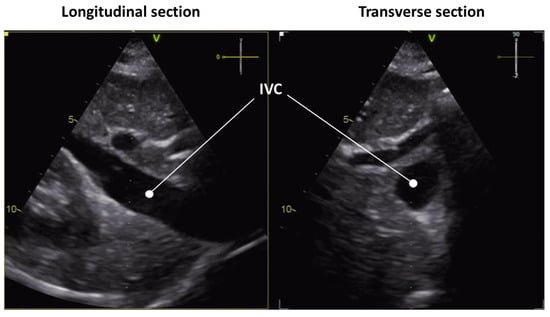

3.1. Longitudinal View

3.2. Transverse View